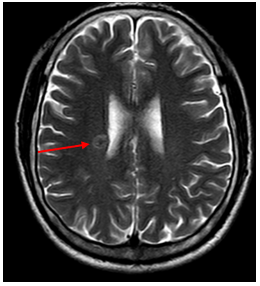

-         Chụp cắt lớp vi tính lồng ngực: phim trước điều trị

Hình 1. Trên phim chụp CT lồng ngực ở cửa sổ nhu mô: thùy trên phổi trái có khối đặc tròn bờ tua gai, kích thước: 29 x20mm, kính mờ và dày kẽ xung quanh, lân cận có nốt bán đặc kích thước 29 x 17mm, ngấm thuốc không đồng nhất sau tiêm, nghi ngờ có phần xâm lấn trung thất trước. Nhu mô thùy còn lại và nhu mô phổi phải lan tỏa các nốt đặc tròn to nhỏ không đều, đường kính: 2-8mm.

Hình 2. Cửa sổ trung thất: Vài hạch trung thất cạnh khí, hạch lớn nhất kích thước 14x7mm

-         Cắt lớp vi tính lồng ngực:

Sau 3 tháng điều trị đích:

U nguyên phát và u thứ phát ở cả 2 phổi đều giảm kích thước rất nhiều, không thấy hạch trung thất.

Sau 6 tháng điều trị:

U nguyên phát chỉ còn kích thước rất nhỏ, u thứ phát 2 bên phổi đã mất hết.